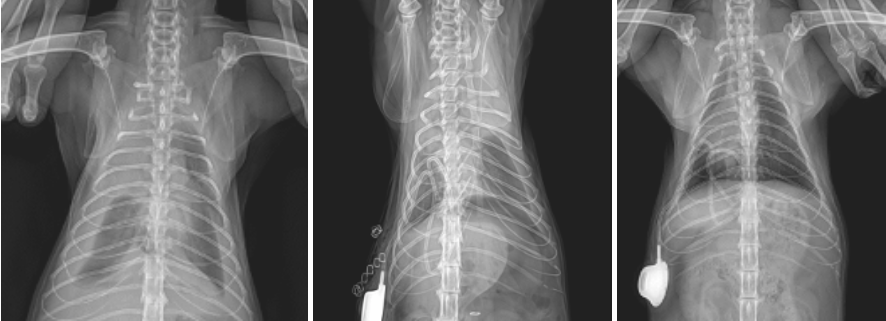

3️⃣ 흉관 포트 삽입

수술 중 흉강 내 잔여 액체 제거 및 재발 시 배액을 용이하게 하기 위해 흉관 포트(Thoracic Port) 를 장착하였습니다. 이를 통해 수술 후에도 흉수를 안전하게 관리할 수 있습니다.

고양이 비장 비만세포종 조직검사 결과

절제된 비장 조직을 다시 한 번 조직검사를 의뢰하였고, 그 결과 고분화형 비만세포종양으로 확인되었으며 수술 경계부는 깨끗하게 절제(margin free)되었습니다. 환자는 수술적 제거 후 항암제 처방이 진행되었으며 수술 이후 현재까지 이상증상, 흉수의 재현 없이 잘 유지되고 있습니다.

고양이 비장 조직검사 결과 – 비만세포종 진단 / 출처: 에스동물메디컬센터

고양이 비만세포종 수술 전(1번) 수술 후(2번) 수술 후 4개월(3번) 방사선 사진 / 출처: 에스동물메디컬센터